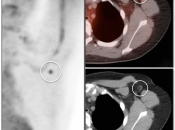

Extravasation of Injected FDG

FDG is injected intravenously. As many cancer patients have challenging venous access issues, partial extravasation of FDG during injection is not uncommon (an estimated 10% of patients have evidence of extravasation on their PET images).

Extravasation of FDG at the time of the intravenous injection can result in false positive interpretations due to:

- Focal intense uptake at the injection site.

- Linear uptake along the lymphatic channels within the arm (appearing as long vessels).

- Focal uptake in small ipsilateral axillary nodes.

If these nodes are enlarged, be cautious before dismissing them as “injection-related”. We have seen more than one case of a radiologist calling axillary nodes “injection-related”, when the patient was injected in the opposite arm.